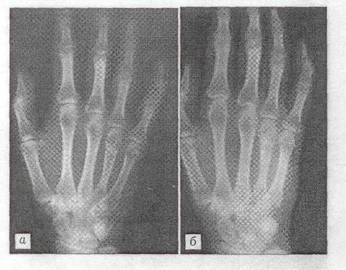

Анализ рентгенограмм показал, что через 1 мес. после хирургических вмешательств картина неоднороной "глыбчатой" структуры в местах заполнения дефектов "Остеоматриксом" или в пространствах между его гранулами и аллоимплантатами, выявлявшаяся сразу после опрерации, полностью исчезала. Рентгеновская ткань была практически однородной и имела умеренныю плотность (рис.1). Через 3 мес. в большинстве случаев (66%), я через 6 мес. у всех больных места, куда помещался "Остеоматрикс", по плотности рентгеновского изображения были неотличимы от окружающей губчатой костной ткани (рис. 2). Признаки перестройки замороженных кортикальных аллоимплантатов, применявшихся совместно с гранулами "Остеоматрикса", во все сроки наблюдения были минимальными (рис. 3), тогда как поверхностно-деминерализованные кортикальные аллотрансплантаты к 6-му месяцу частично инкорпорировались в материнское костное ложе (рис. 4).

Рис.1 Рентгенограмма больной П. 24 лет.

Диагноз: хондрома ΙV пястой кости. а - после операции с пластикой дефекта "остеоматриксом"; б - через 1 мес.

Больная К., 51 года, поступила в отделение костной патологии ЦИТО 21.05.01 с жалобами на боли в области ΙΙΙ пястно-фалангового сустава правой кисти, усиливающиеся при физической нагрузке. При клинико-рентгенологическом обследовании выявлен очаг патологической деструкции в головке ΙΙΙ пястной кости (рис, 5 а). Диагноз: хондрома ΙΙΙ пястной кости. 22.05.01 произведена операция: краевая резекция ΙΙΙ пястной кости, удаление патологической ткани с последующей электрокоагуляцией стенок полости и-пластикой дефекта "Остеоматриксом" (рис. 5 б). Послеоперационное течение без осложнений. Рентгенологическая картина через 1 и 5 мес после операции свидетельствует о постепенной биодеградации пластического материала и замещении его собственной костной тканью (рис. 5 в, г).

Рис.5 Рентгенограмма больного К. 51 года.

Диагноз: хондрома ΙΙΙ пястной кости. а - до операции; б - после операции с пластикой дефекта "Остеоматриксом"; в - через 1 мес.; г - через 5 мес.